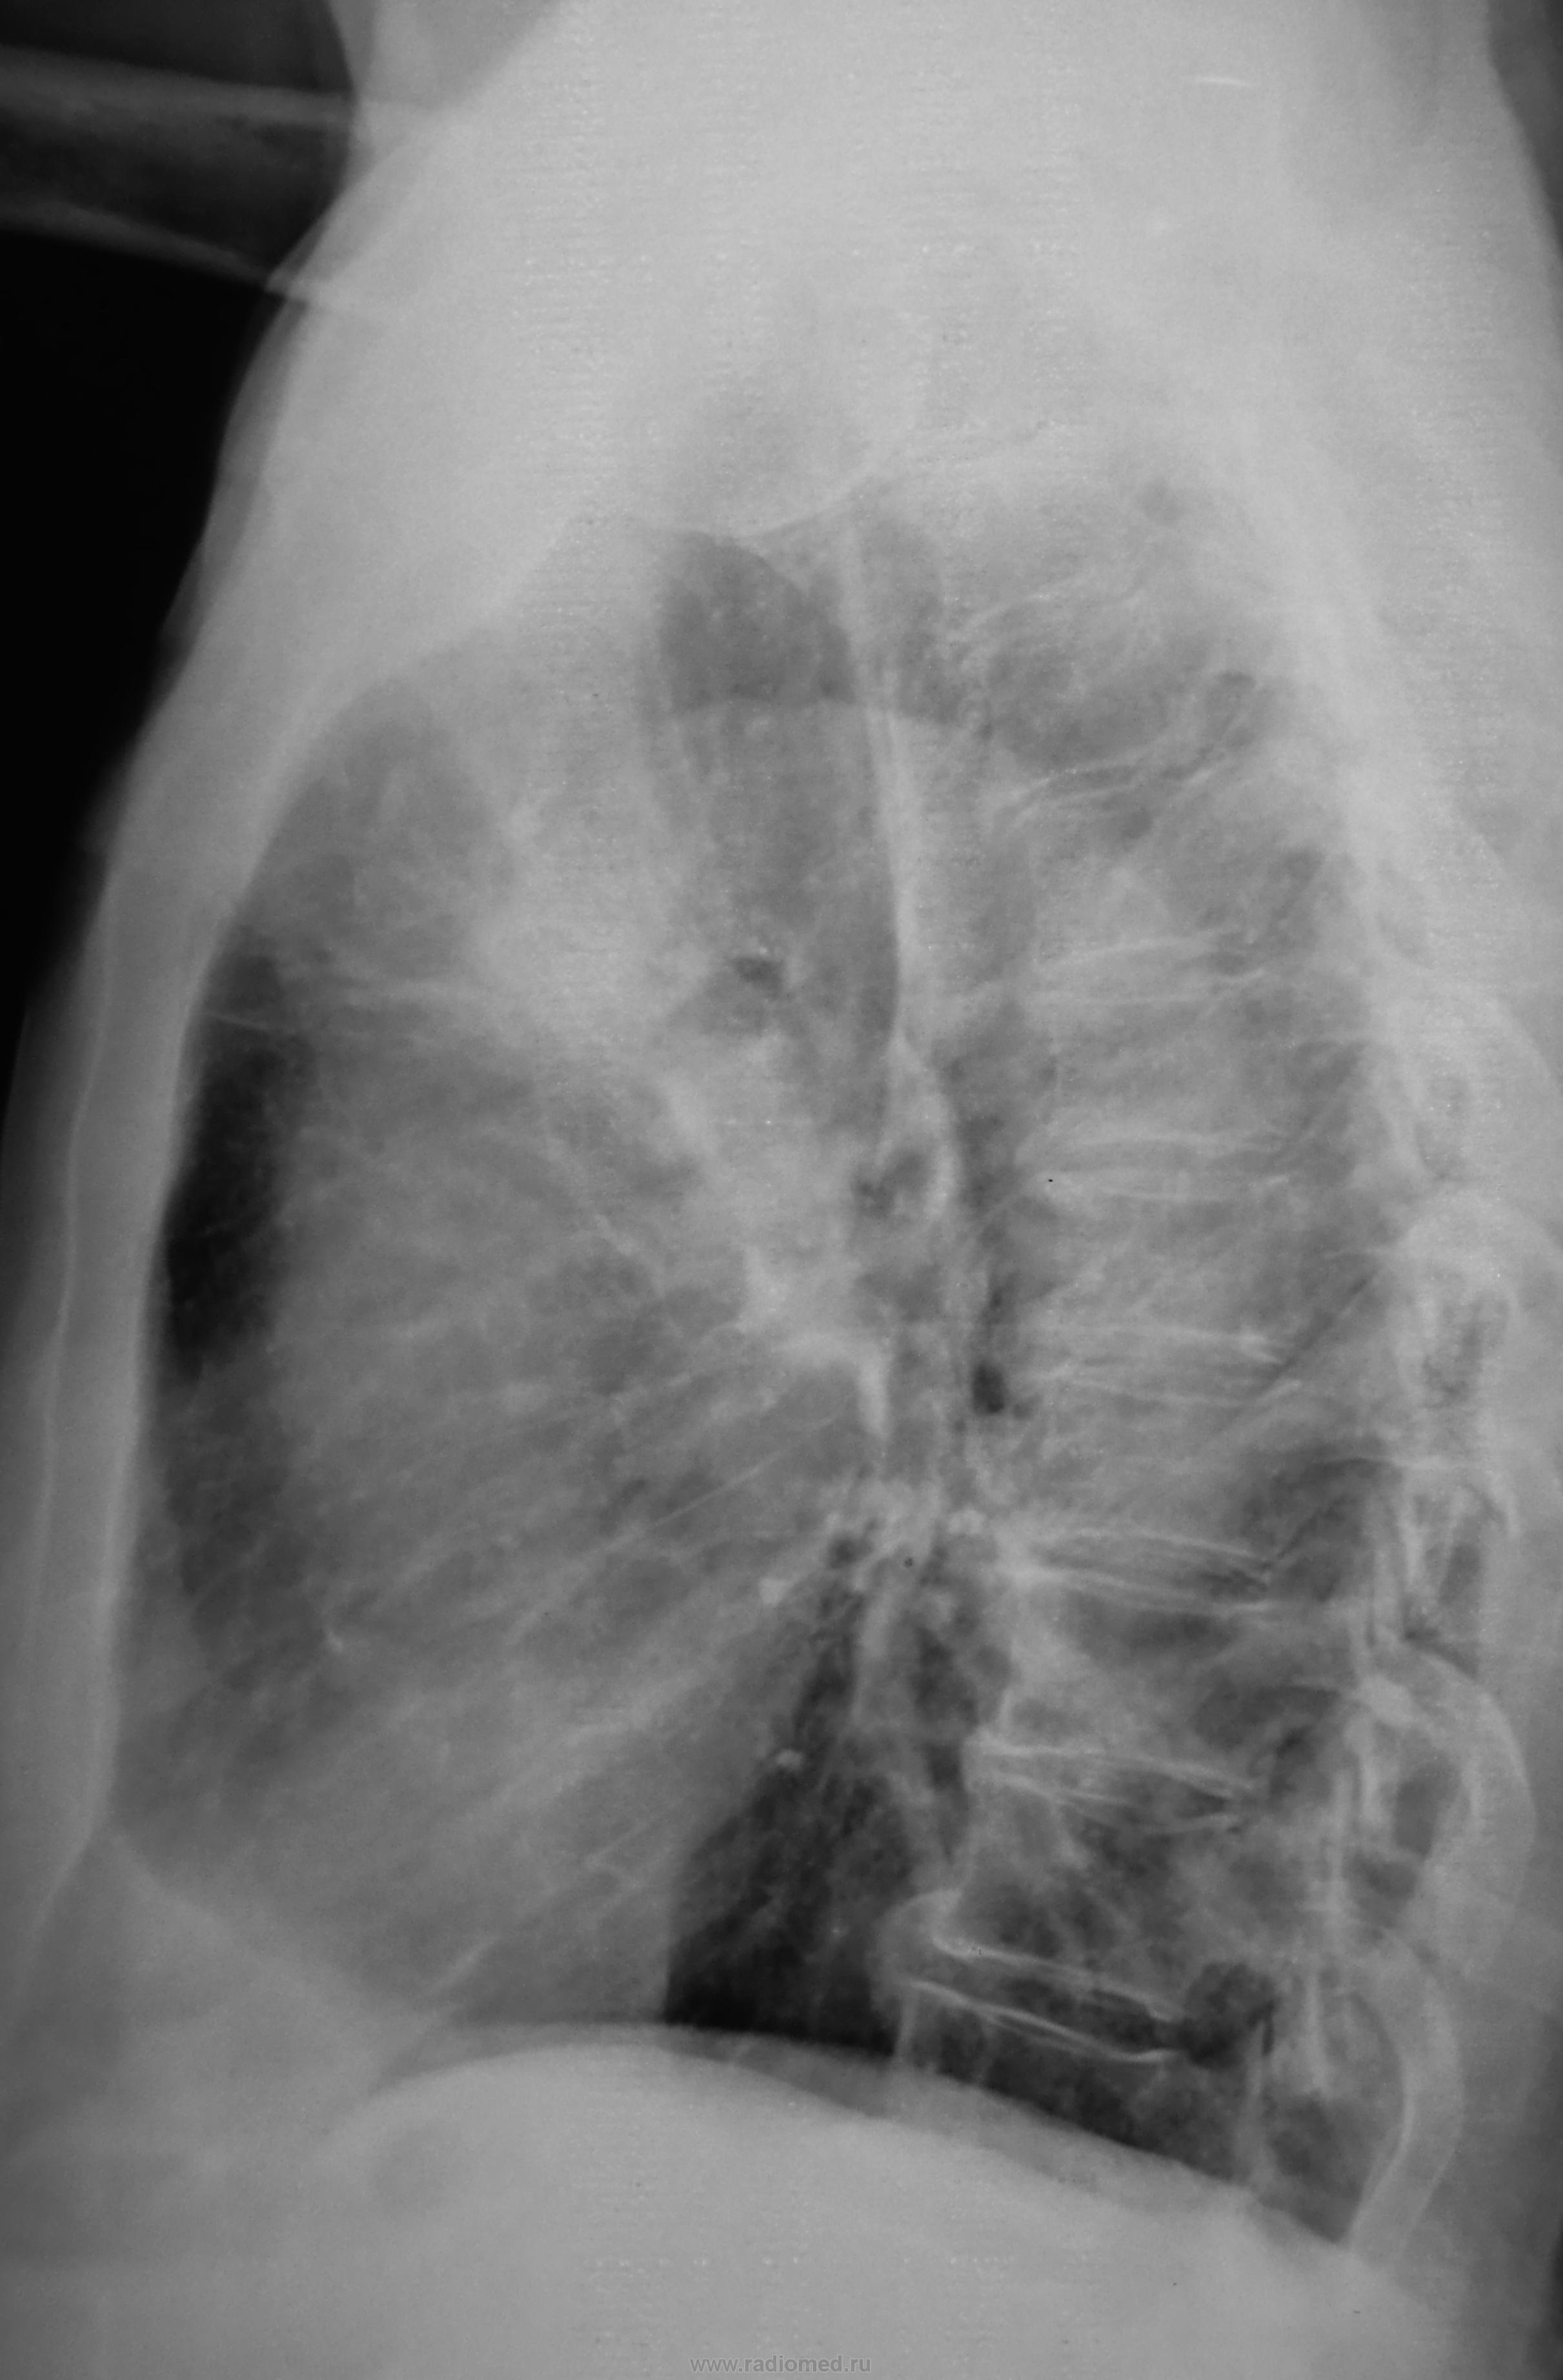

На опухоль походит

Вероятно периферический, не исключена централизация на ВДБ. Ждем томограмок..

ВДБ (ну, или трешка) слева с субателектазом.

На лицо явно гиповентиляция S3

Центральный слева.

Рак центральный с поражением B3,ателектаз S3,междолевой плеврит.